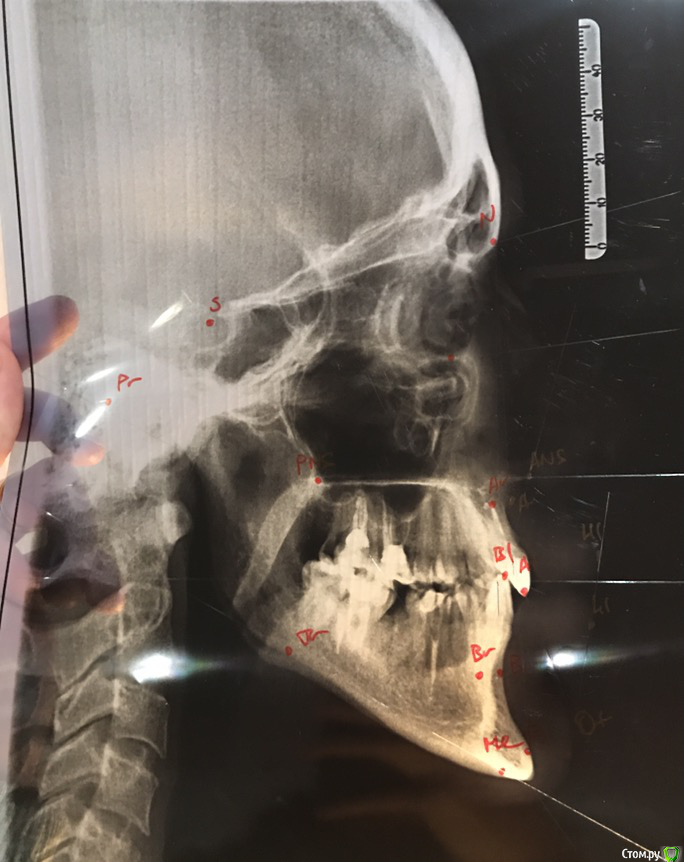

Ситуация сложная, что вполне видно на фотографиях.

верхние 1,1,2 штифты

нижние 1,1 штифты. 6-ка слева под удаление. 5-ка сверху нависает.

7-ка верх слева удалена, на ее месте стоит 8-ка (пульпит)

6-ка справа внизу удалена, 8ка справа сверху удалена.

Много депульпированных зубов, почти везде пломбы.

Имеется щелчок в суставе, но сустав не болит. Щелчки периодичные, не постоянные.